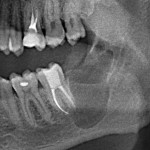

Это мой самый любимый и тщательно подготовленный проект — семинар по немедленной имплантации. Он уже дважды был в Москве, и однажды — в Нижнем Новгороде. На этот раз, мы проводим его совместно с компанией APEX в Санкт-Петербурге, и посвящен он будет… догадайтесь с трех раз?))) Через фокус немедленной имплантации будут рассмотрены различные имплантационные системы, операции остеопластики, синуслифтинга, удаления зубов и превентивной аугментации лунок.